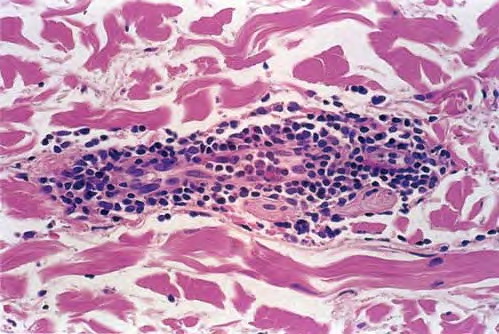

Erythema Chronicum Migrans =الحمامى المزمنة الهاجرة